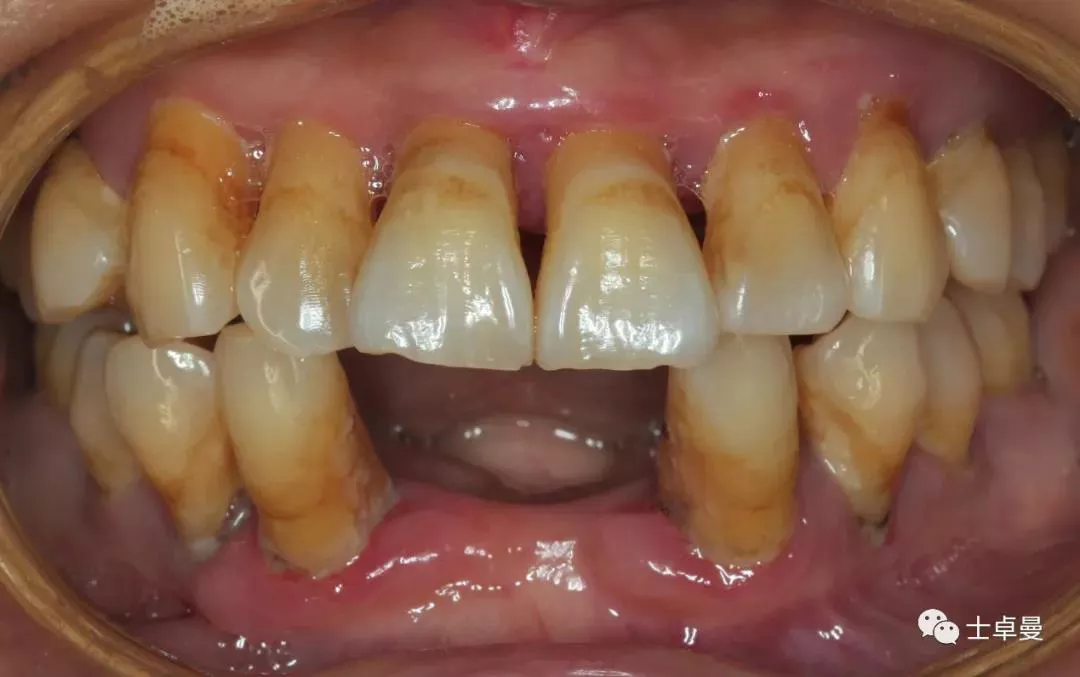

· 临床检查:17、37、32-42、37缺失;

· 前牙区牙齿扇形移位,口腔卫生状况较差;

· 菌斑指数:2;

· 牙石指数:3,色素 (+);

· 牙龈颜色暗红,肿胀,质地松软;

· 口内余留牙松动度II°~III°;

根分叉病变III°~IV°。